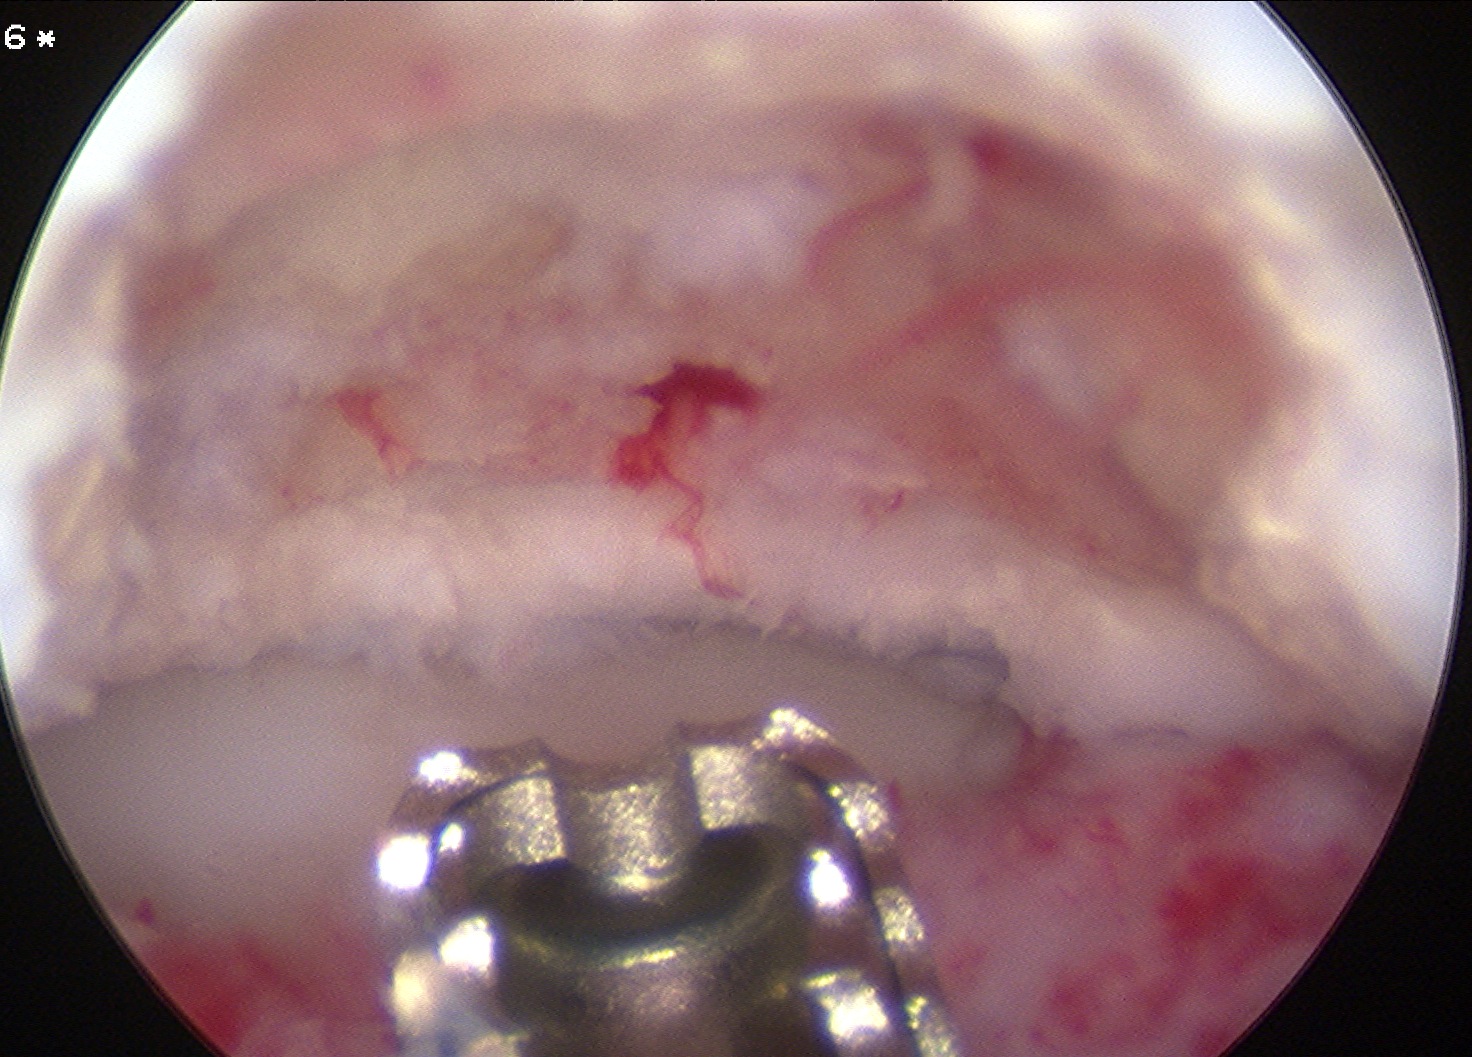

Arthroscopic debridement of loose fragments +/- marrow stimulation

Technique

Elbow arthroscopy

Posterior portals

- capitellar OCD viewed by flexing elbow

Arthroscopic debridement of loose fragments

Arthroscopic debridement of loose fragments and microfracture

Arthroscopic debridement of loose fragments and abrasionplasty